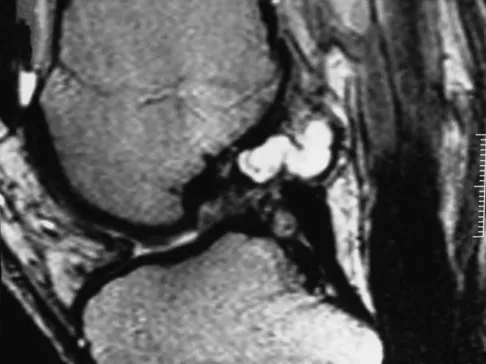

Question 10

A 51-year-old male truck driver has had progressive left hip pain for more than 2 years, and he reports that the pain has become severe in the past 9 months. He is now unable to work because of the pain. Examination reveals that range of motion of the hip is limited to 95 degrees of flexion, 0 degrees of internal rotation, and 20 degrees of external rotation. The plain radiograph, MRI scan, and intraoperative gross photographs are shown in Figures 9a through 9d. Management should consist of

Explanation